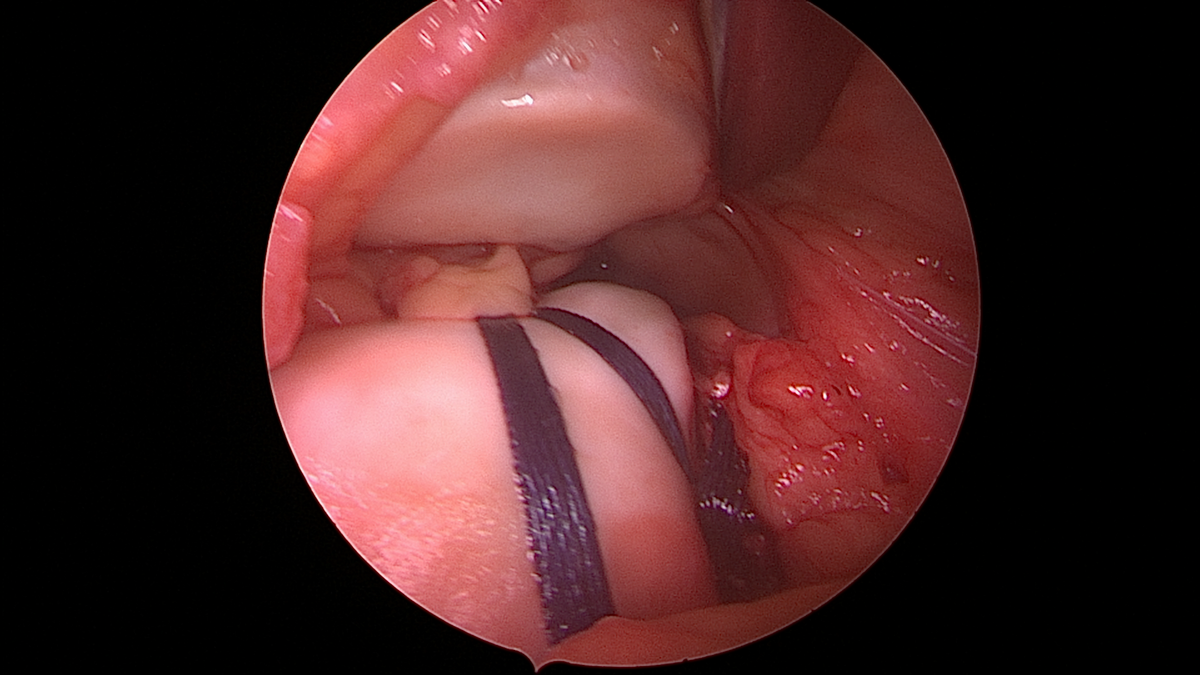

Patellainstabilitäten

Die Instabilität der Kniescheibe betrifft häufig junge Patienten. Nach der ersten Luxation der Kniescheibe erfolgt eine ausgiebige Diagnostik, um mögliche Risikofaktoren auszuschließen. Dabei wird sowohl die Beinachse beurteilt, die Stellung der Kniescheibe selbst, die knöcherne Gleitrinne (sogenannte Trochlea) und auch die Rotation des Beines. Schlussendlich wird für jeden Patienten eine individuelle Therapieempfehlung ausgestellt.

Häufig ist aufgrund des hohen Rezidivrisikos jedoch eine operative Therapie nötig.  Das Halteband der Kniescheibe (sogenanntes MPFL) wird dabei durch eine körpereigene Sehne ersetzt und etwaige Zusatzeingriffe stabilisieren das Gesamtsystem zusätzlich. Teilweise muss die Gleitrinne vertieft werden („Trochleaplastik“), teilweise ist eine Begradigung oder Korrektur der Beindrehung nötig, teilweise muss der Ansatz der Kniescheibensehne versetzt werden („Tuberositasversatz“).